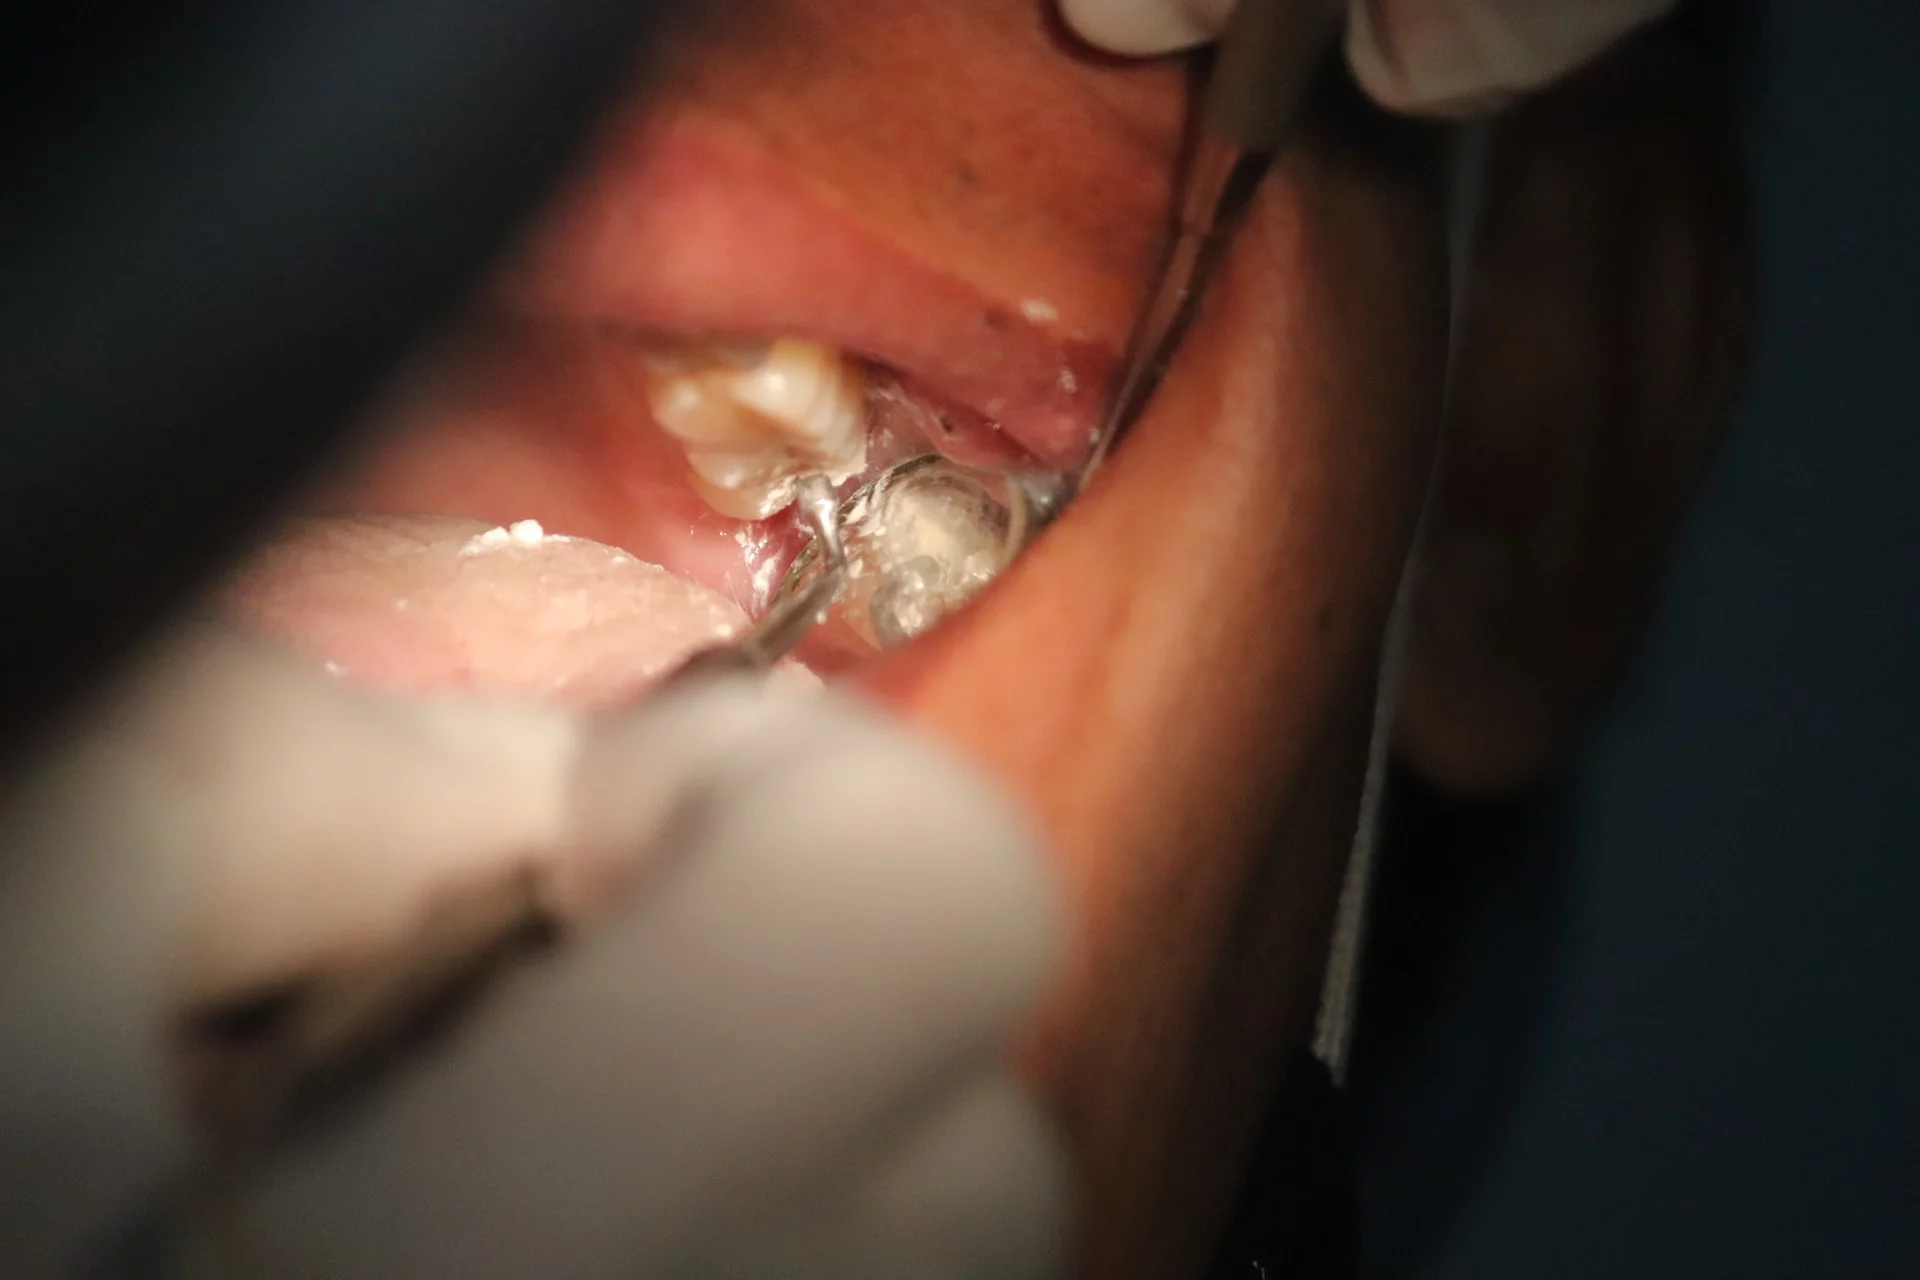

Die Behandlung von Karies zwischen den Zähnen hängt vom Grad der Schädigung ab. Bei festgestellter Karies wird zunächst der betroffene Bereich sorgfältig entfernt. Dies geschieht, um sicherzustellen, dass alle kariösen Zahnstrukturen beseitigt sind und eine Ausbreitung der Karies verhindert wird. Anschließend wird dieser Bereich mit einer Füllung versehen. Die Füllungen können aus verschiedenen Materialien wie Amalgam, Komposit, Keramik oder Gold bestehen. Die Wahl des Materials hängt von verschiedenen Faktoren ab, wie der Position des Zahnes, der Größe der Füllung und ästhetischen Überlegungen.

Bei fortgeschrittener Karies, insbesondere wenn ein großer Teil des Zahnes betroffen ist, kann eine Krone notwendig sein. Eine Krone ist eine Art Kappe, die über den beschädigten Zahn gesetzt wird, um ihn zu schützen, seine Funktionalität wiederherzustellen und sein Erscheinungsbild zu verbessern. Sie kann aus verschiedenen Materialien wie Porzellan, Keramik oder Metalllegierungen hergestellt werden. Die Krone wird individuell angefertigt, um sich nahtlos in das Gebiss einzufügen.

In Fällen, in denen die Karies so tief ist, dass sie den Nerv des Zahnes erreicht, kann eine Wurzelkanalbehandlung erforderlich sein. Bei diesem Verfahren werden das infizierte oder abgestorbene Nervengewebe, die Bakterien und der Zahnabfall aus dem Inneren des Zahnes entfernt. Nach der Reinigung und Desinfektion der Kanäle wird der Zahn mit einem speziellen Material gefüllt und versiegelt, um eine weitere Infektion zu verhindern. In vielen Fällen wird nach einer Wurzelkanalbehandlung eine Krone auf den behandelten Zahn gesetzt, um seine Stabilität und Funktionalität zu gewährleisten.